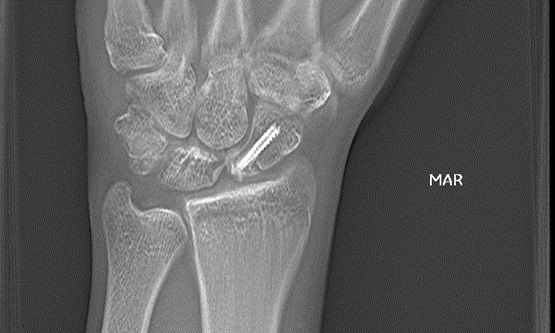

Samir Mehta, M.D.,

Chief of Orthopaedic Trauma & Fracture Service and Assistant Professor of Orthopaedic Surgery at the University of Pennsylvania, presents 2 fracture cases that involve hardware.

"What we can get with advanced imaging is an ability to understand our fracture pattern when it's out of plane. VolumeRAD really does this very well"

David E. Quinn, M.D.,

Board Certified Orthopedic Surgeon at the Capital Region Orthopaedics, Albany, NY, discusses three upper extremity cases.

"As orthopedic surgeons, we're trying answer some very simple questions especially with respect to fracture care ... Is there a problem? Does the patient need an operation or is it indicated? Has it been done properly? Is the problem resolved? I've found that digital tomosynthesis helps answer these questions in a substantial percentage of cases with minimal risk and minimal expense."